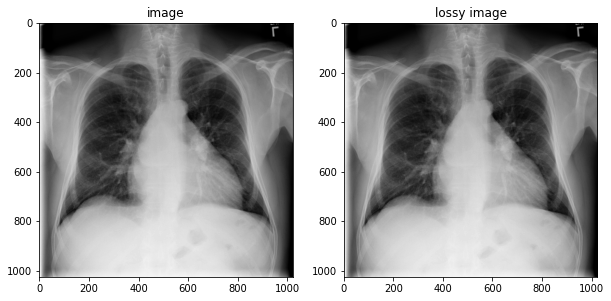

image = tfio.image.decode_dicom_image(image_bytes, dtype=tf.uint16)

lossy_image = tfio.image.decode_dicom_image(image_bytes, scale='auto', on_error='lossy', dtype=tf.uint8)

fig, axes = plt.subplots(1,2, figsize=(10,10))

axes[0].imshow(np.squeeze(image.numpy()), cmap='gray')

axes[0].set_title('image')

axes[1].imshow(np.squeeze(lossy_image.numpy()), cmap='gray')

axes[1].set_title('lossy image');